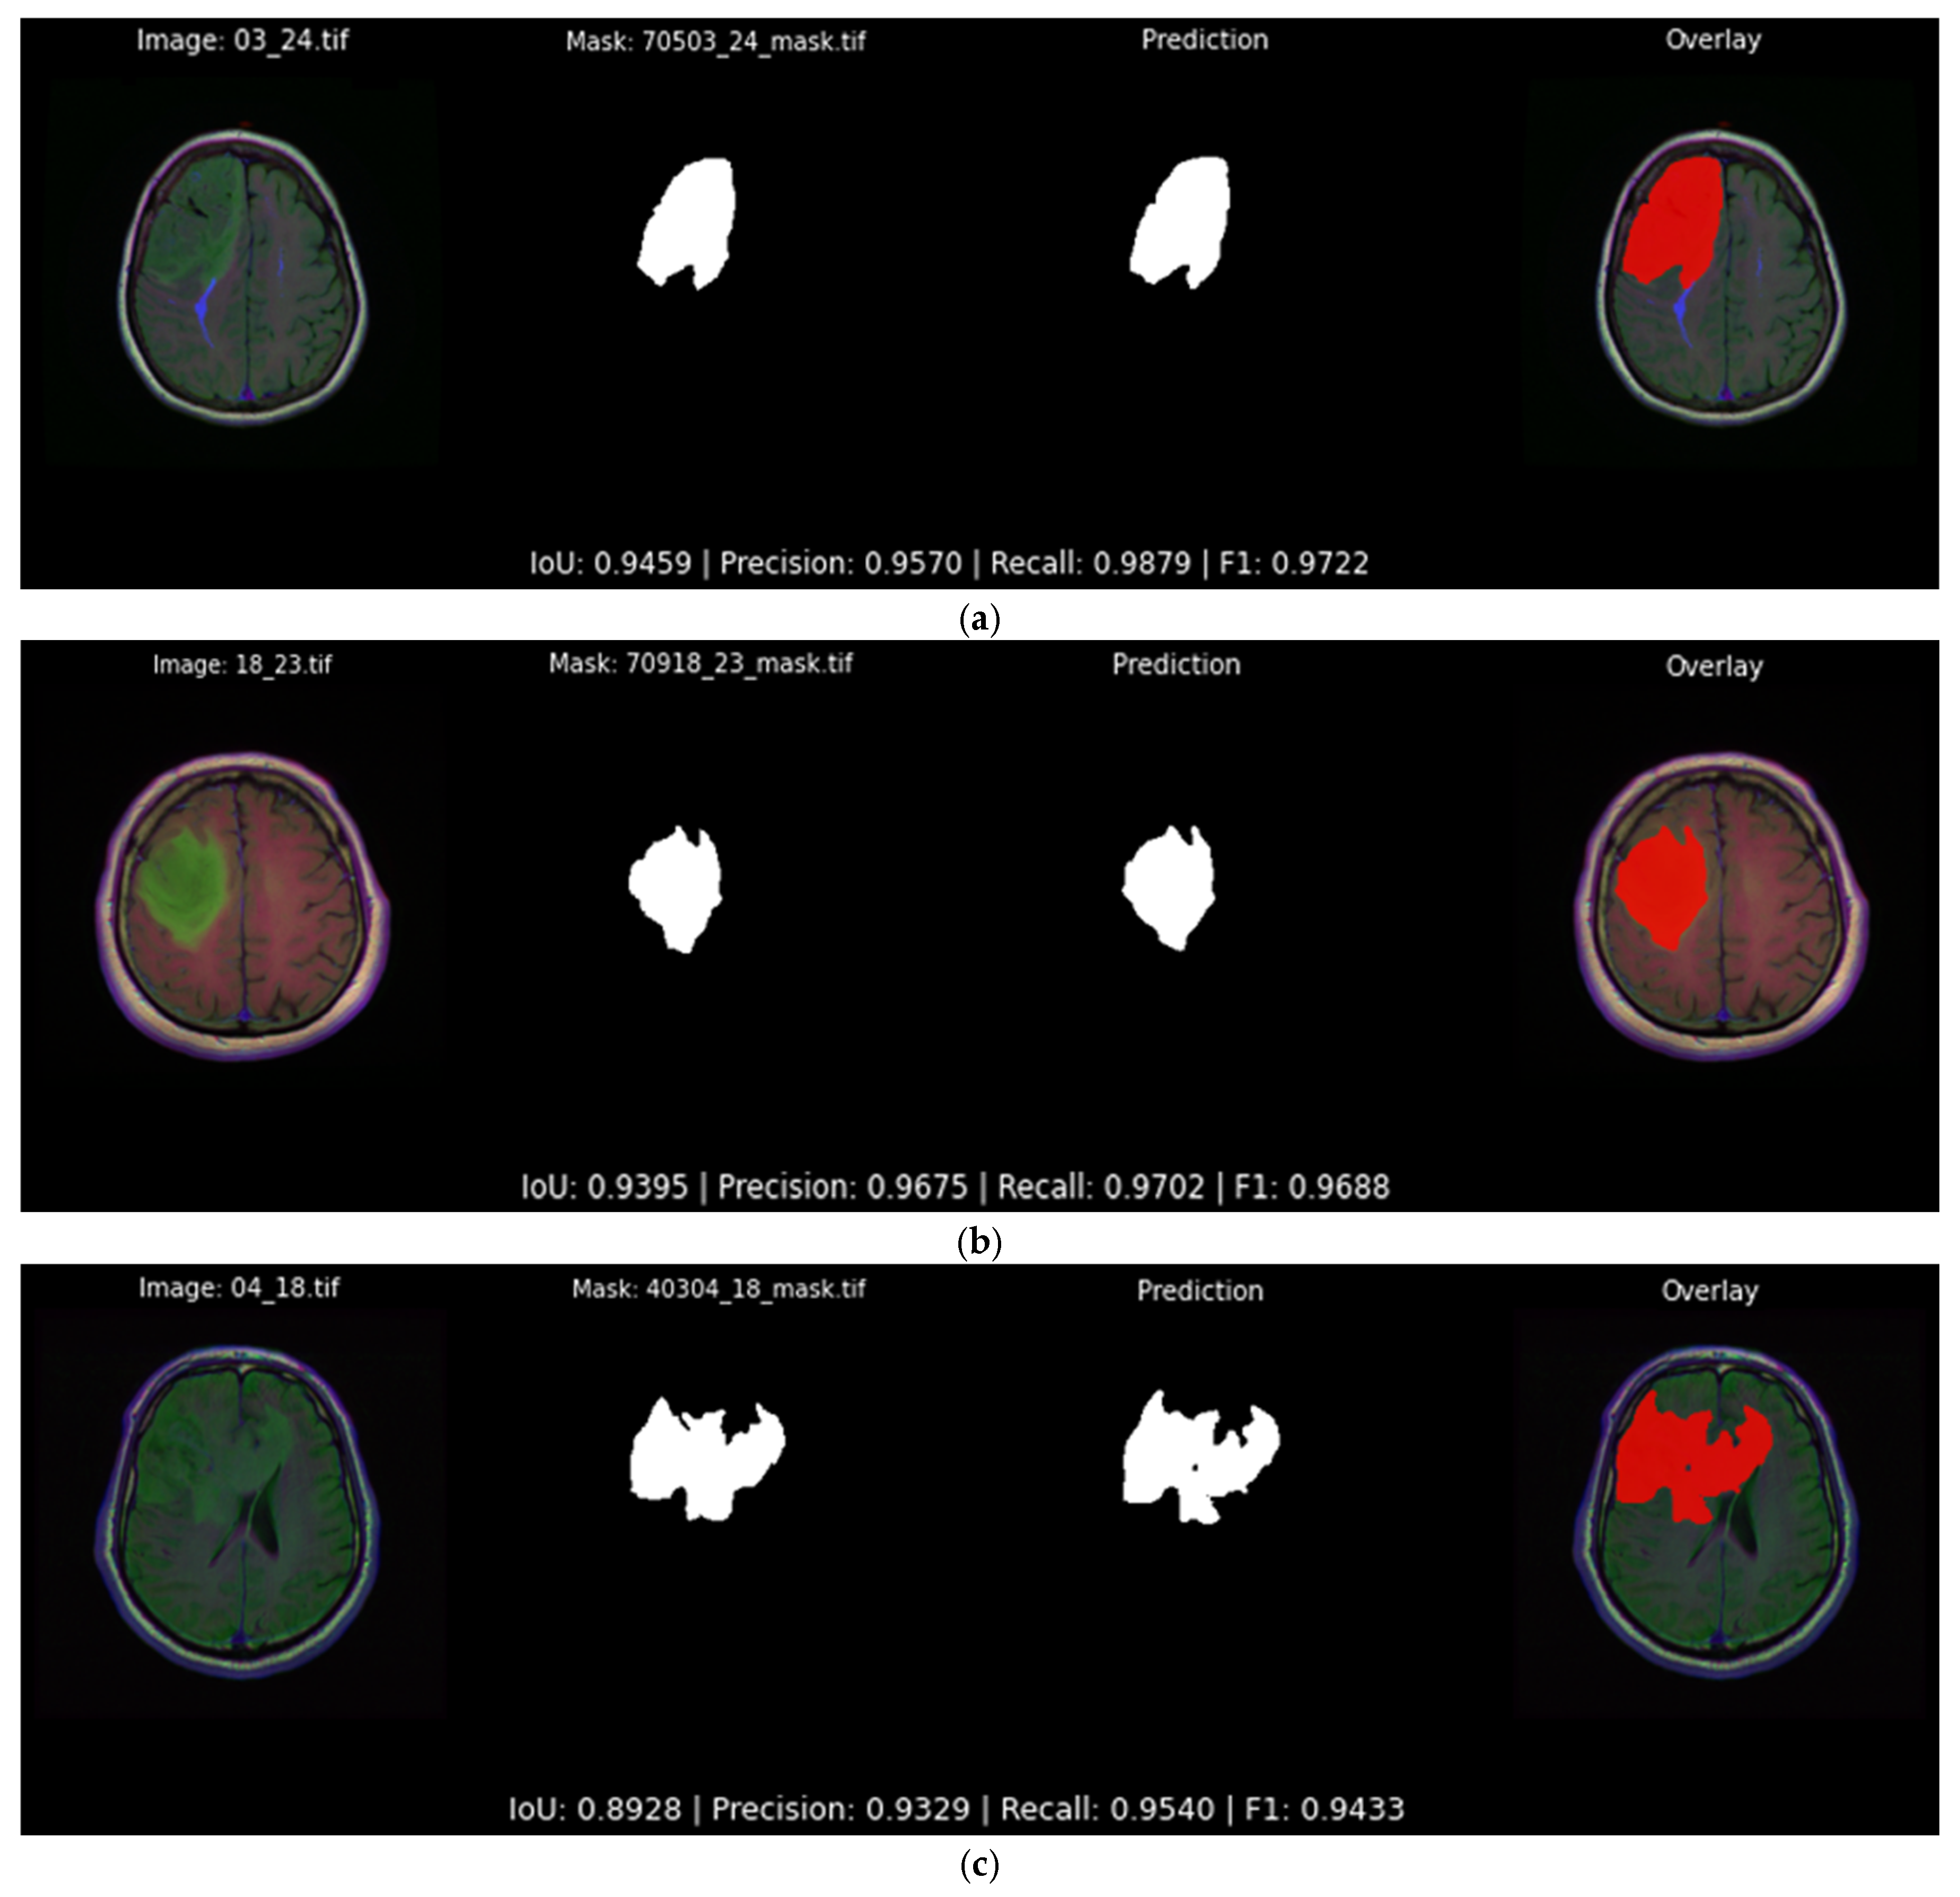

4.2. Qualitative Results

| Accurate segmentation | Figure 13 | Predicted masks closely follow tumor boundaries and details | 0.946, 0.940, 0.892 |